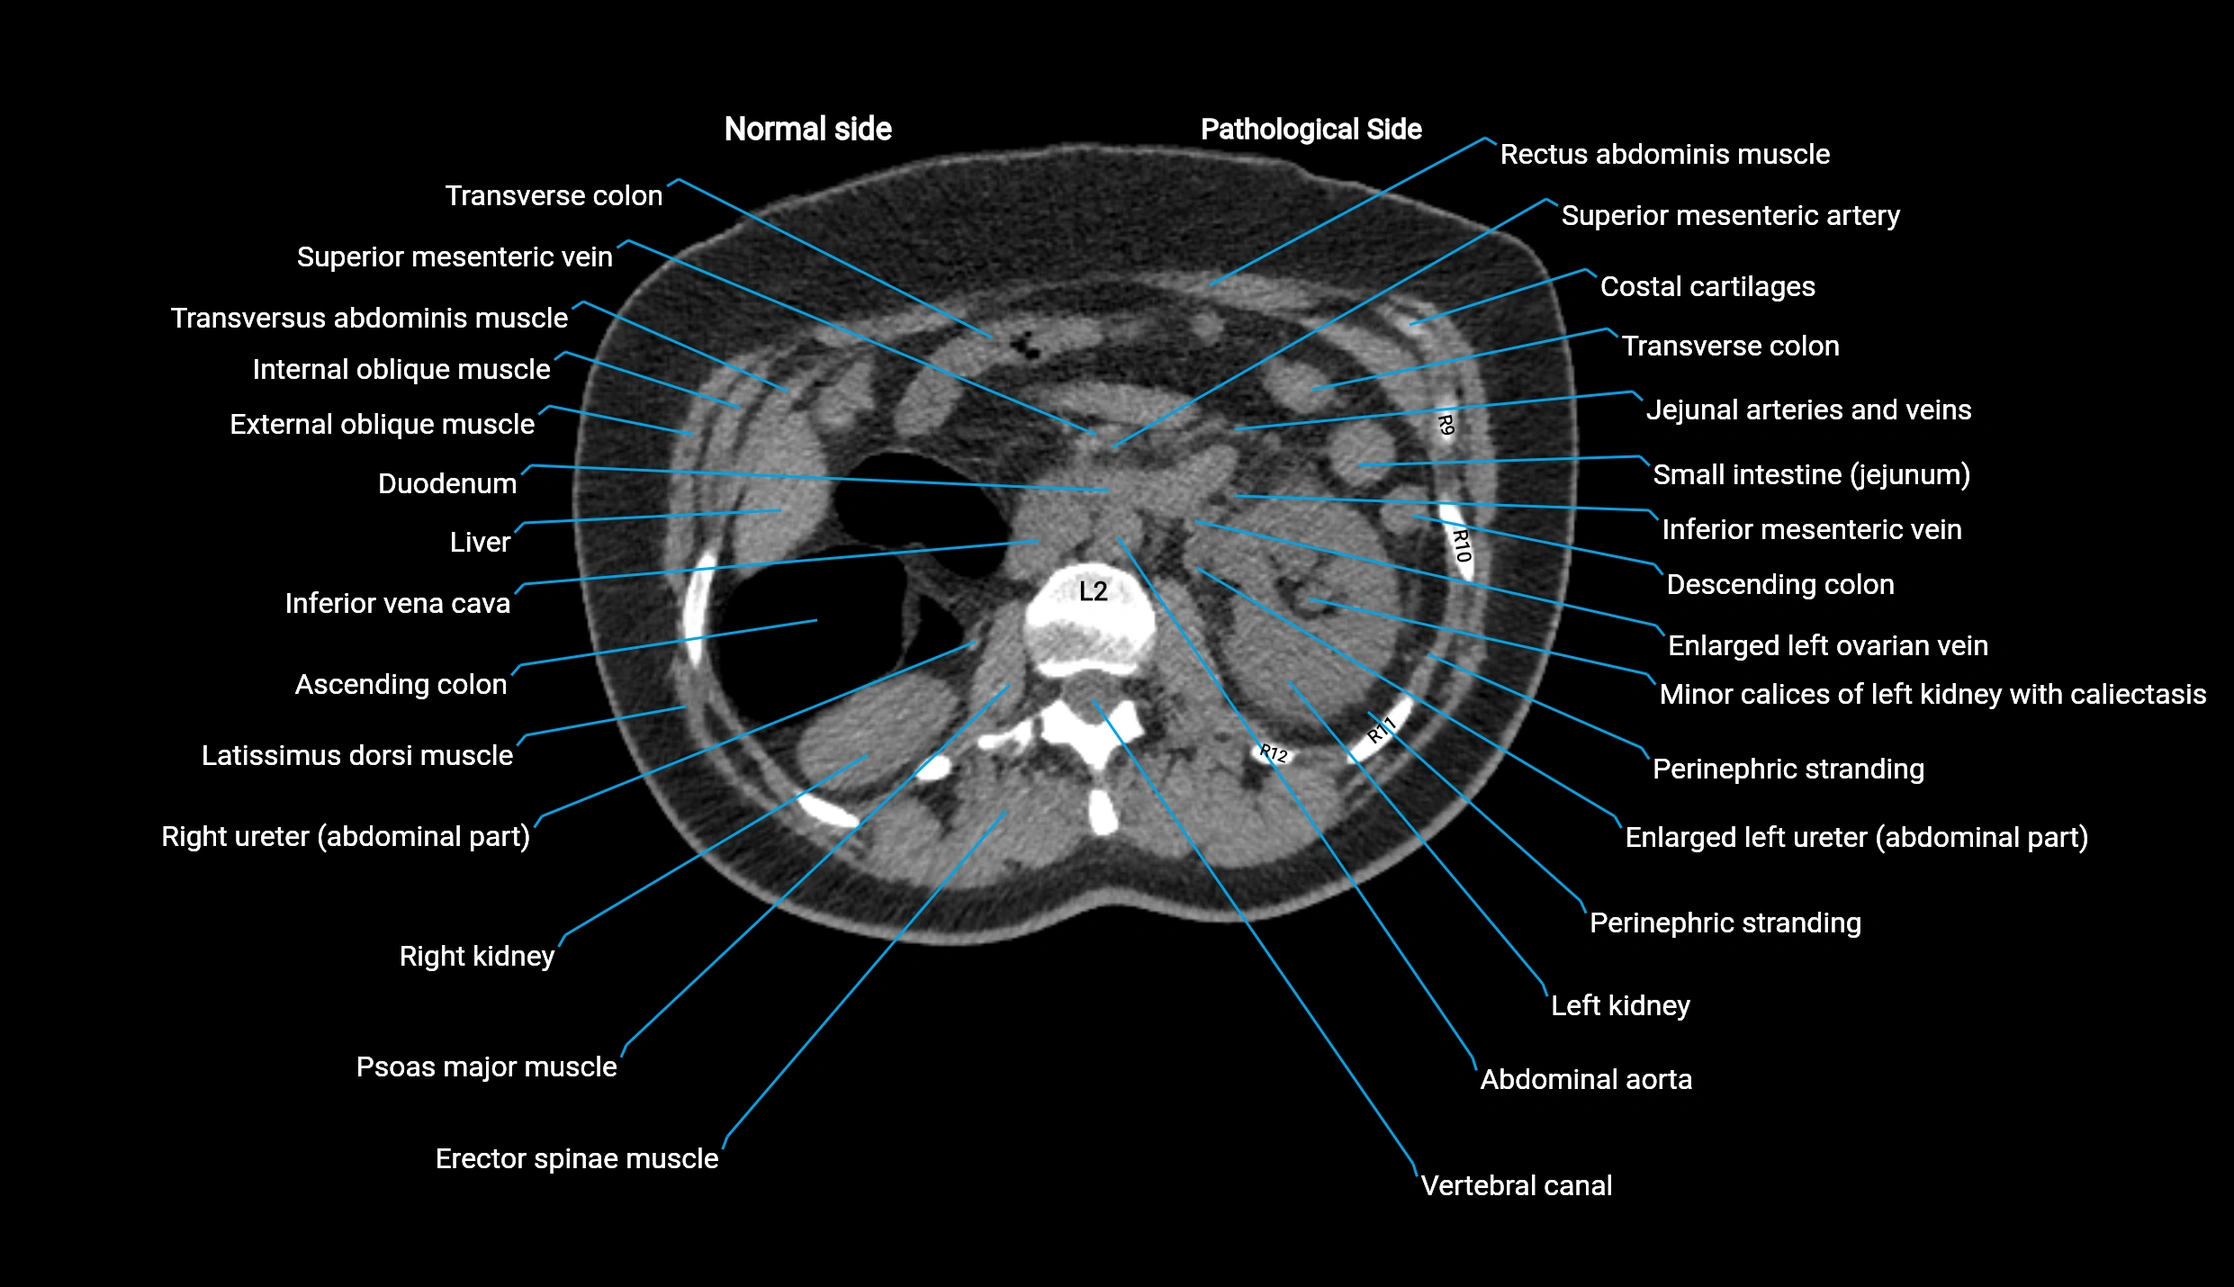

CT image

image